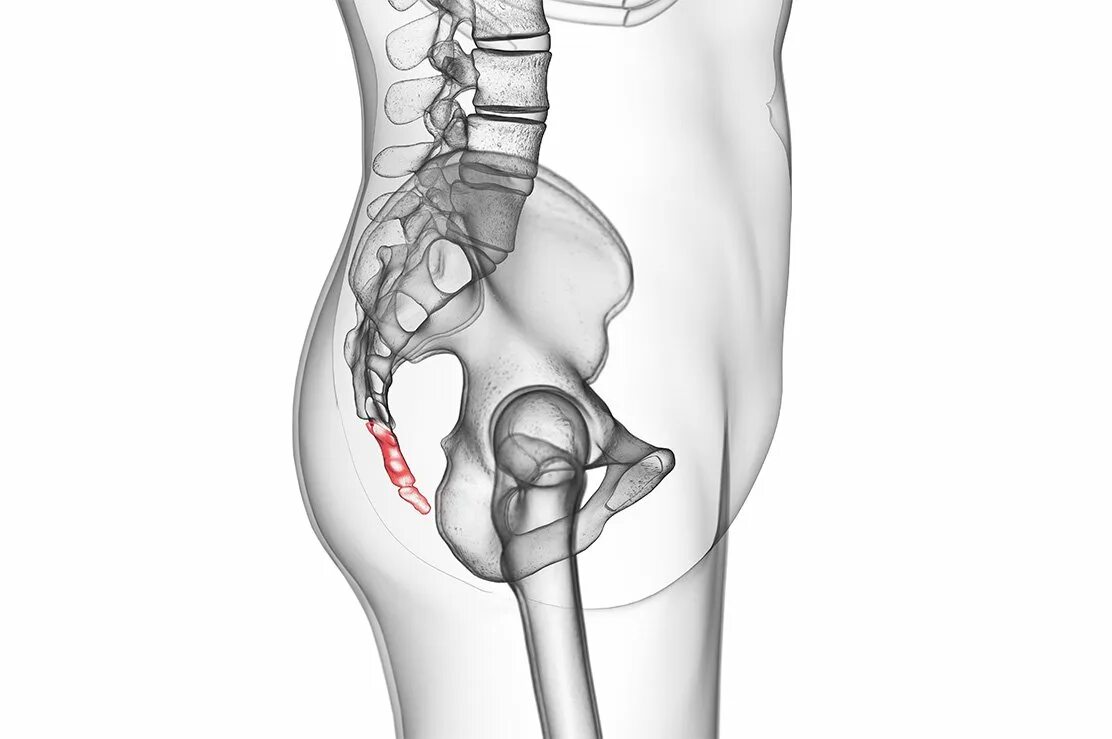

Горяев тазобедренного сустава